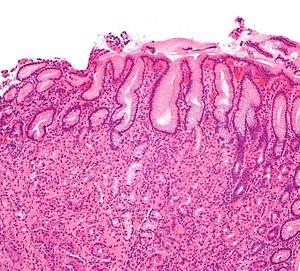

Gastritis helicobacter - intermed mag.jpg

Micrograph showing gastritis. H&E stain.